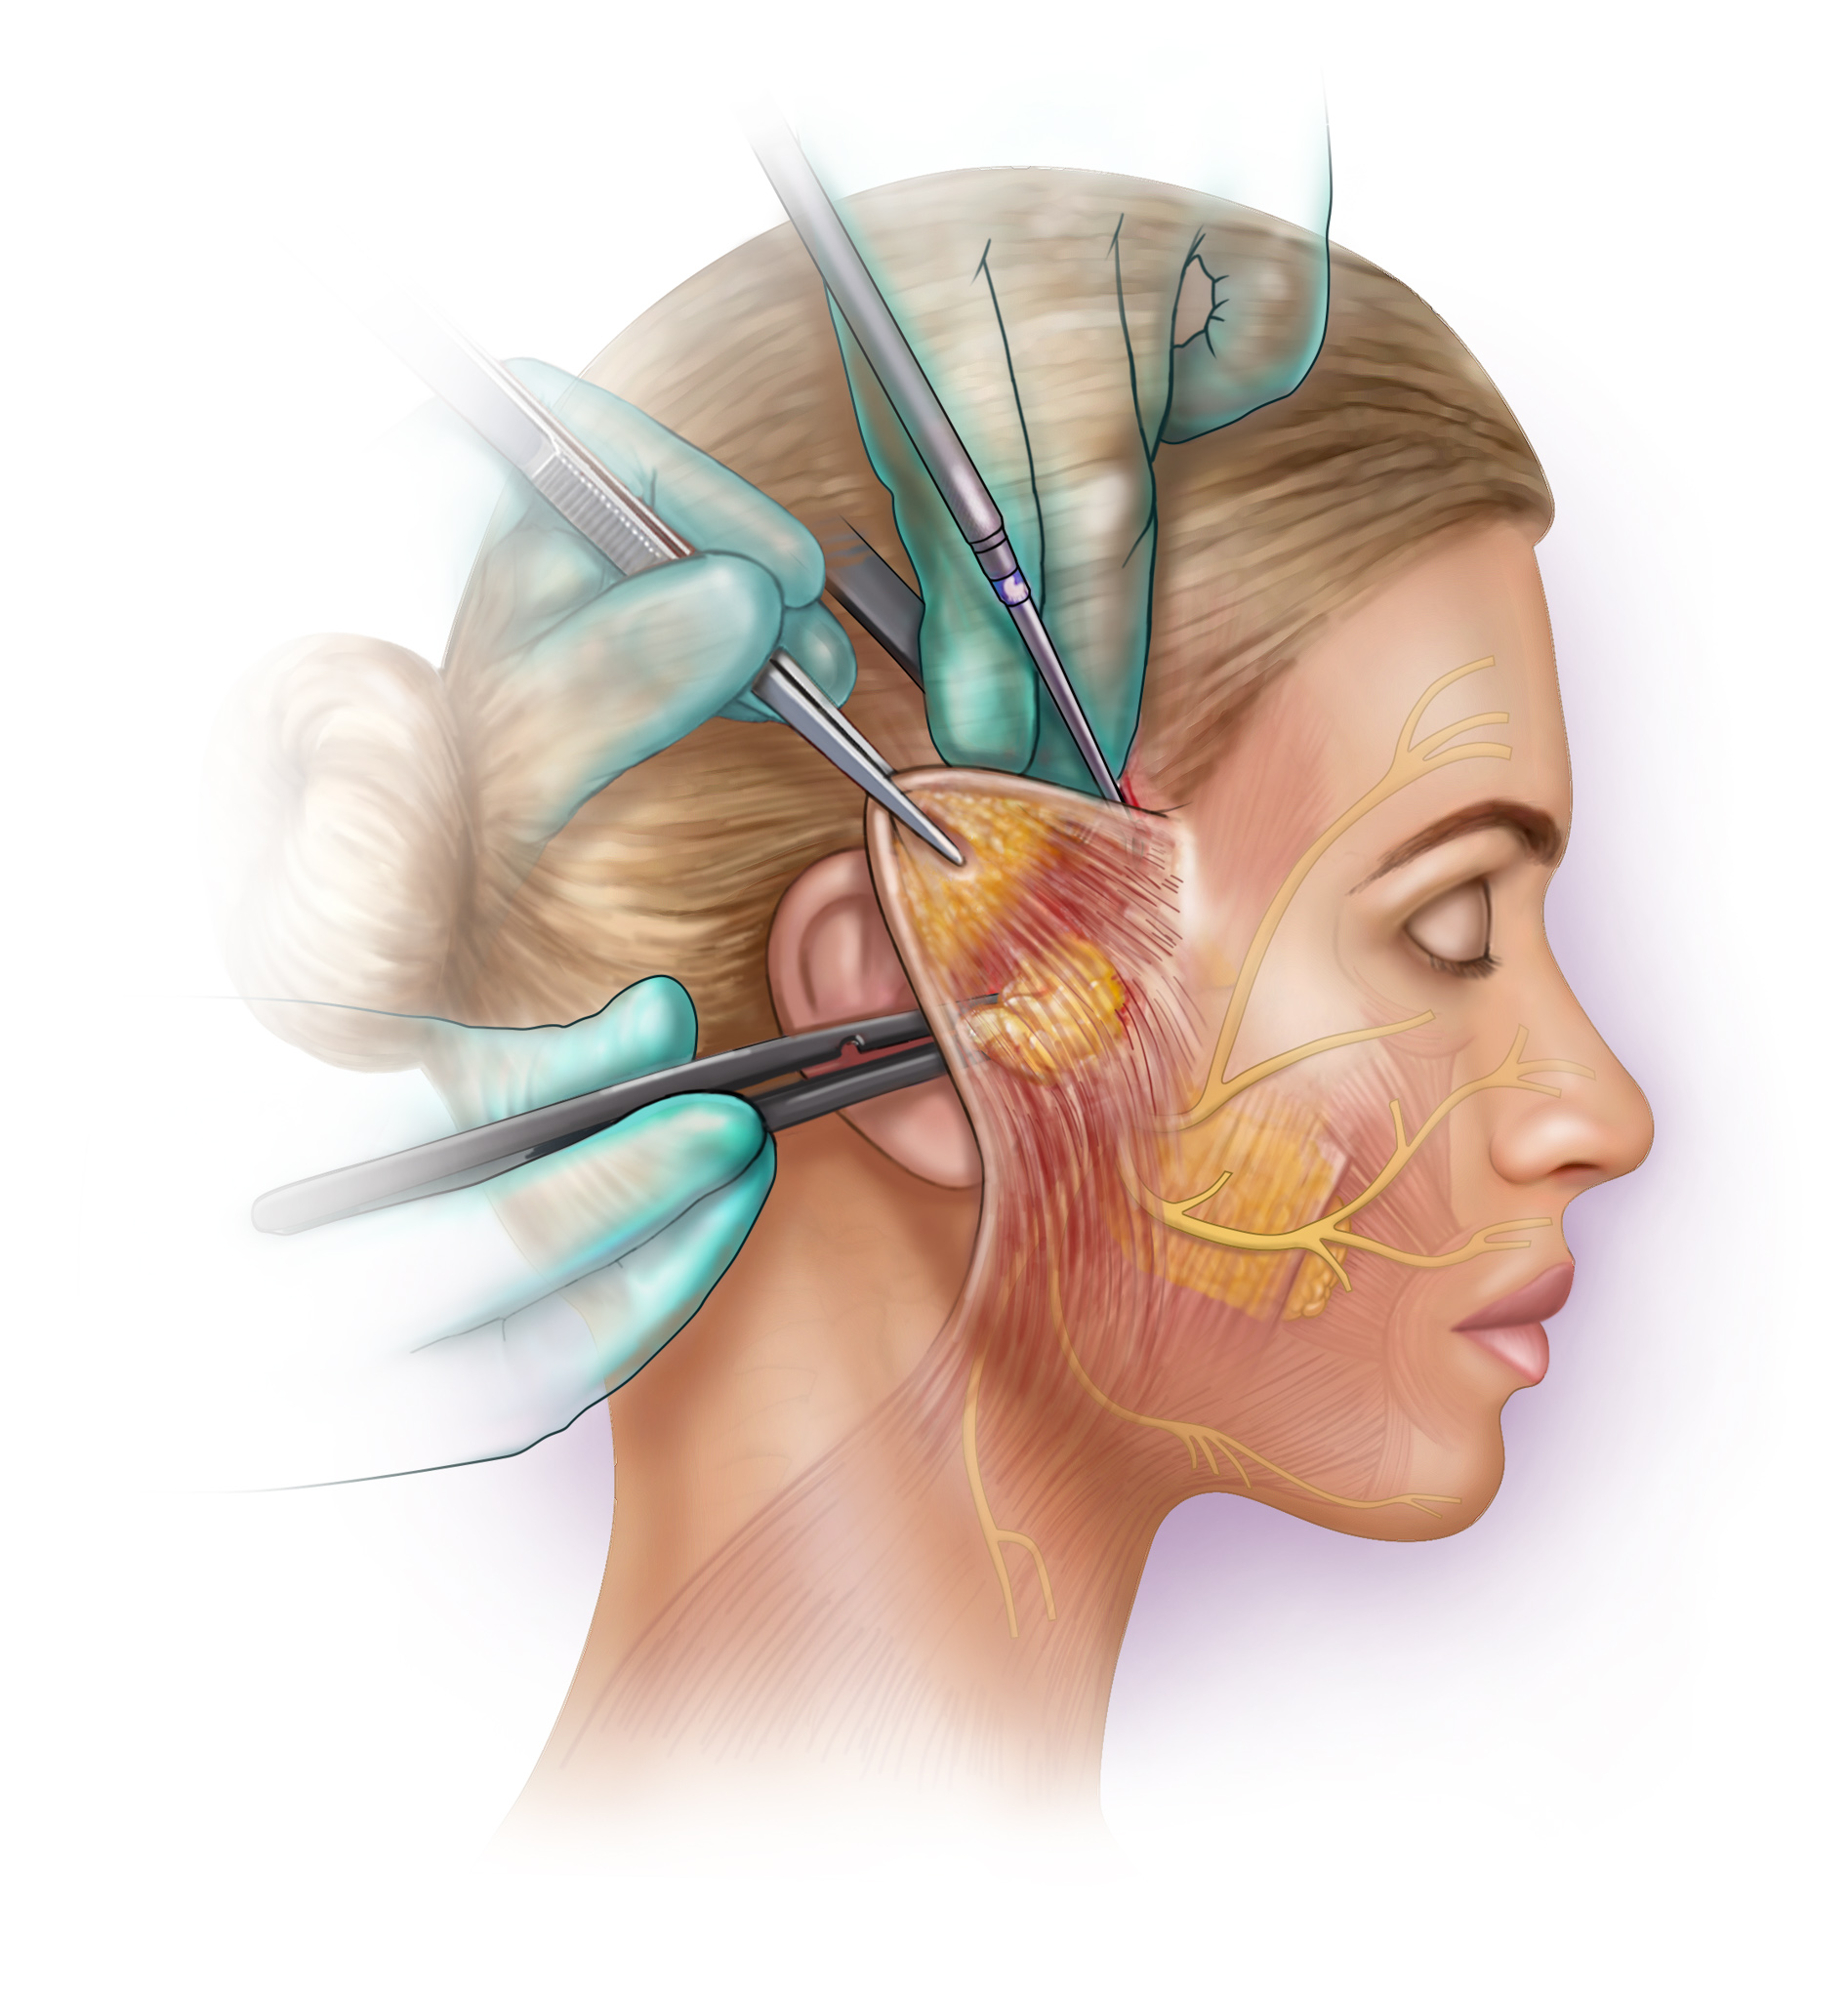

I am a medical illustrator! I wanted to be a doctor and was enrolled in premed, then received a few flyers for colleges in the mail for medical illustration. I decided to change my major from premed to medical illustration. I studied at two private colleges in a combined program for art and medicine.

I create medical illustrations, animations, interactive projects and timelines for physicians, attorneys, medical device and pharmaceutical companies to create illustrations for educational purposes.

I am proud to educate people. To scientifically visualize what’s unseen by the naked eye for the general public!

Image Credits

Lindsay Coulter